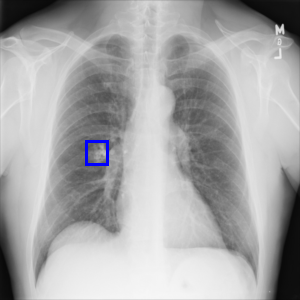

Examples of abnormal images generated by the proposed simulator are shown in the Figure 4.

Figure 4: Examples of abnormal images generated by the proposed simulator. The left is a normal lung image, and the middle is the abnormal image generated by the simulator. In the right, the location where the lesion has been inserted in the middle image is visualized by the blue bounding box.